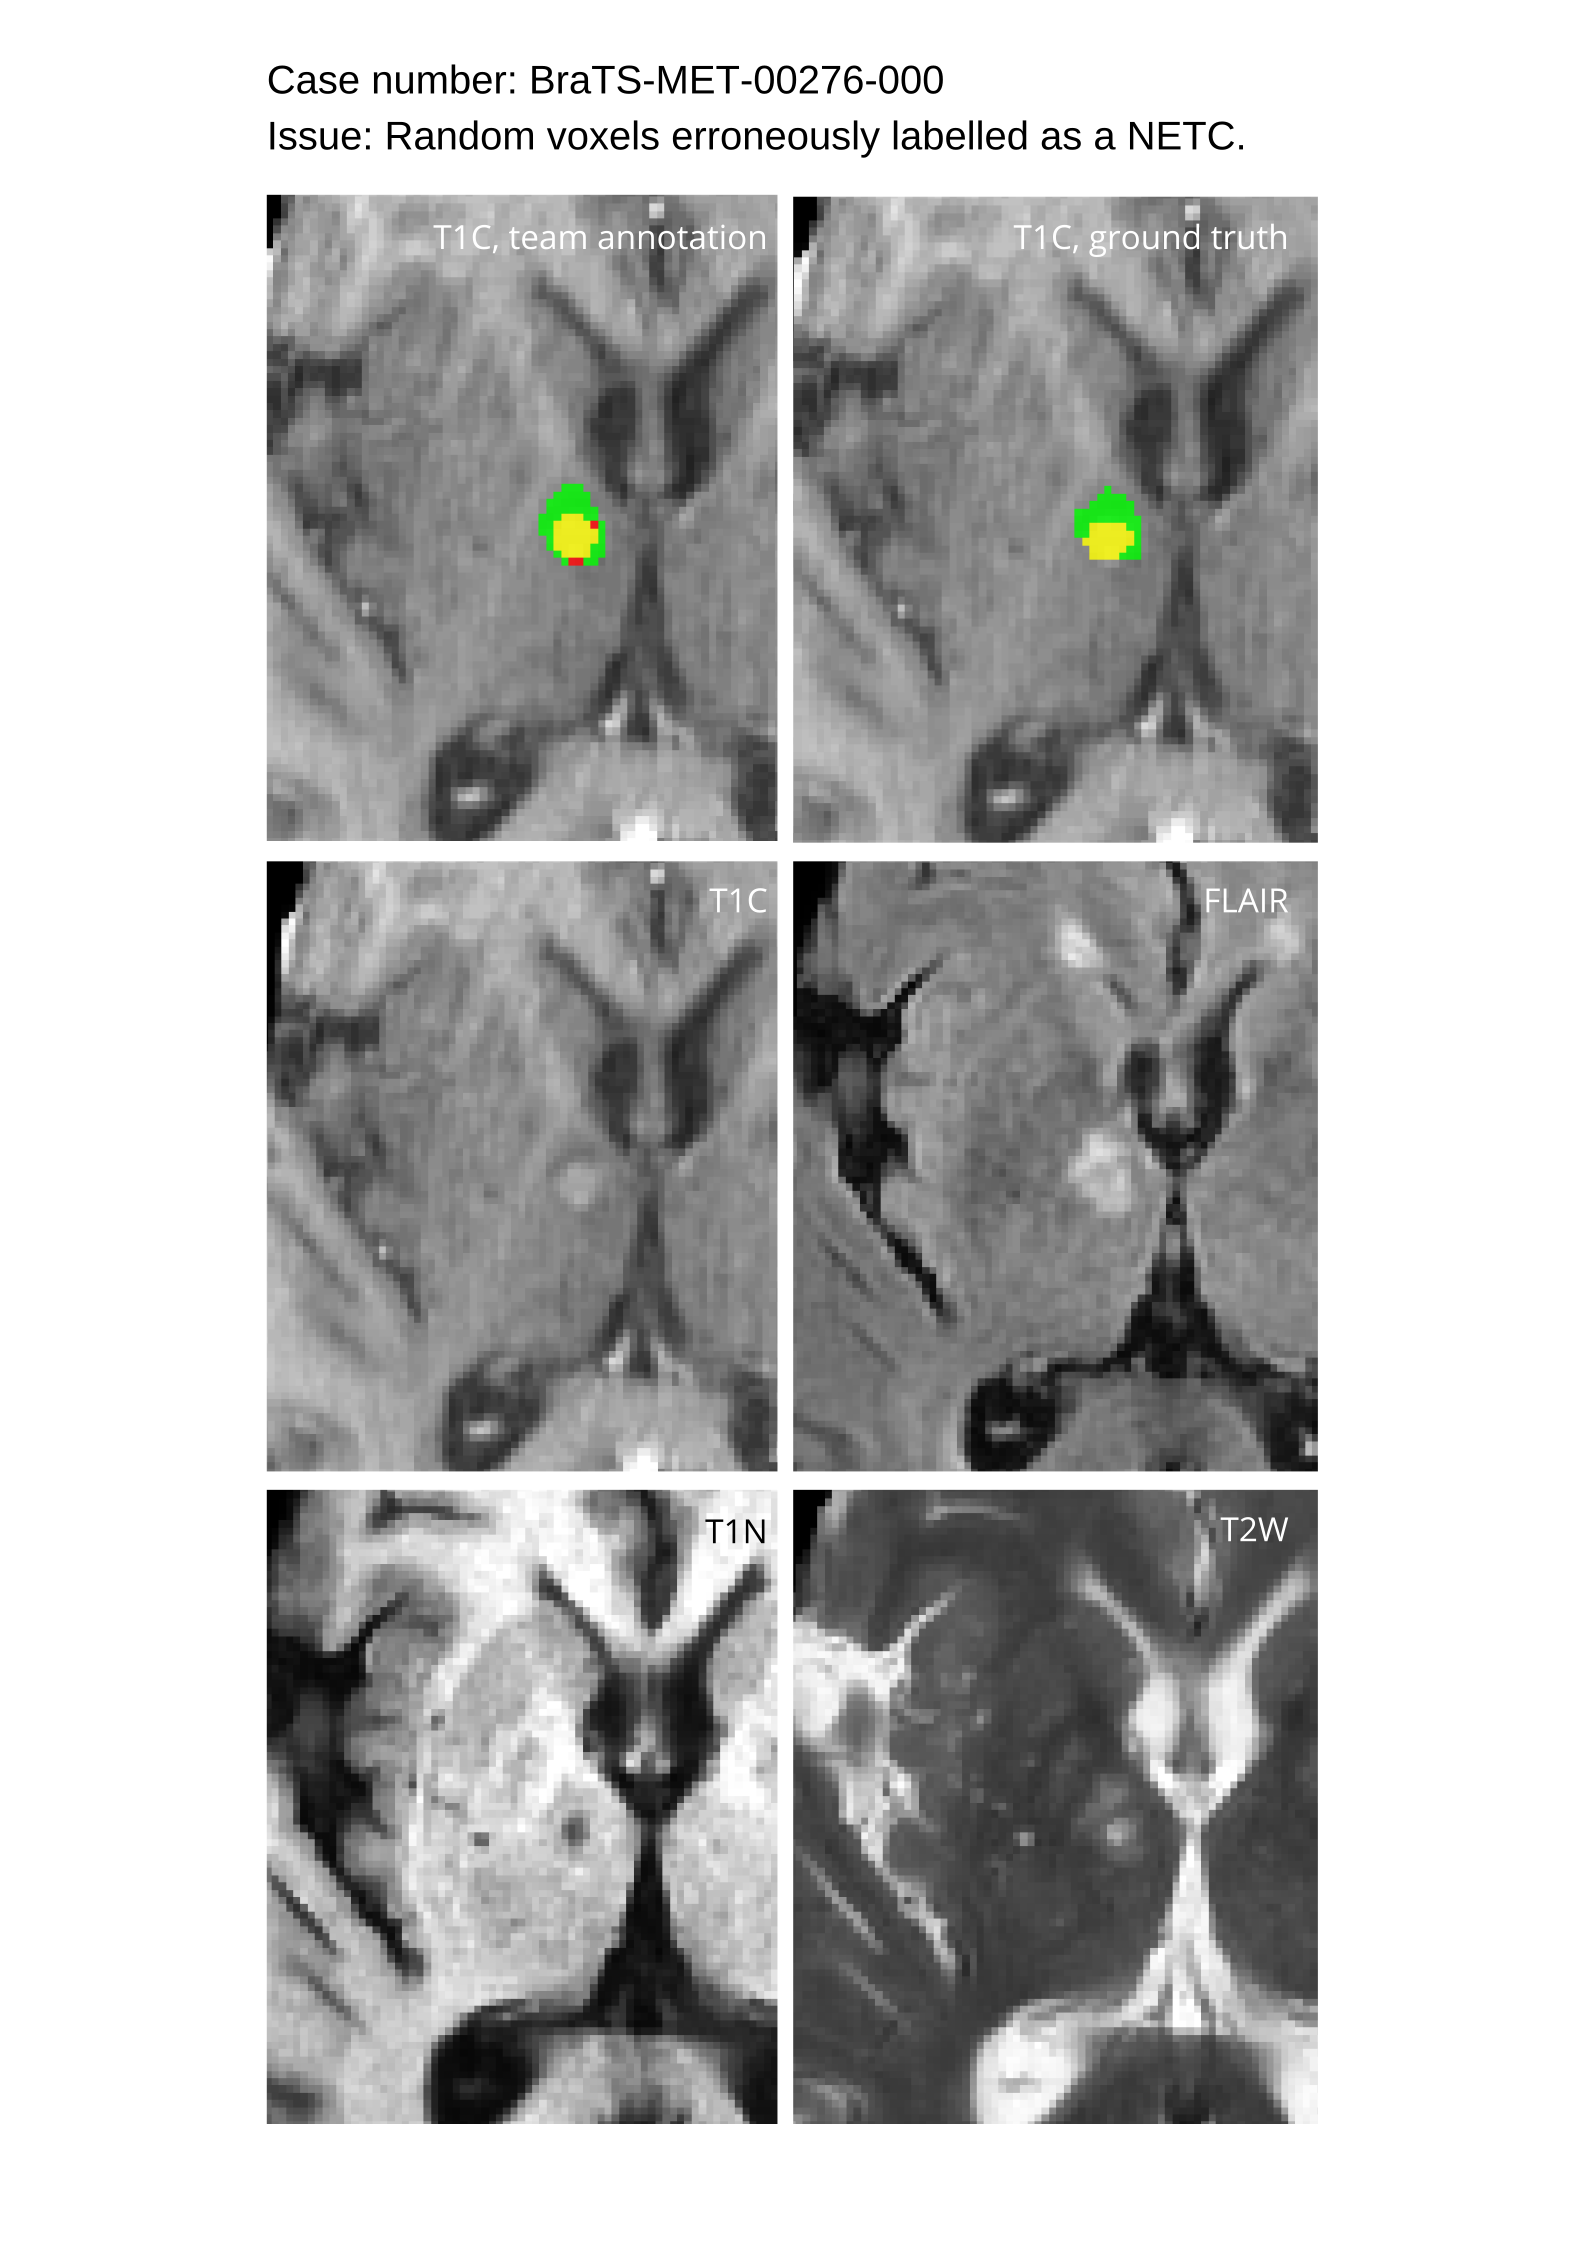

Approvers reviewed the volunteer annotations and either approved the case or returned it to students for re-annotation. Additionally, a QC process was implemented, which included removing all random voxels and any voxels outside the brain mask, ensuring all images had the same parameters (space, orientation, and origin) as the SRI24 atlas, and verifying the presence of all segmentations and segmentation masks are in the folder with original NIfTI images.